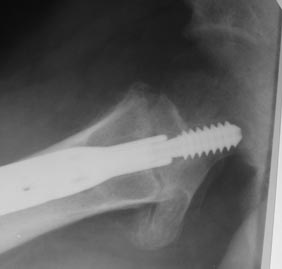

Уважаемые коллеги! Нужен совет. Появился такой больной Х., 23 года. Травма 26.11.2013г. оступился в снегу, получил закрытый межвертельный перелом левого бедра.

Оперирован 09.12.2013г. Последние две недели ходил с тростью, занимался ЛФК. Движения в левом тазобедренном суставе безболезненные, незначительно ограничены. Три дня назад появились ноющие боли в нижней трети левого бедра , субфебрилитет после физнагрузки.

Из обследования, пока, сделанные сейчас снимки.

Д-з: миграция конструкции, АНГБК?

На сагитальных снимках DHS смещен вниз похоже?,те динамическая компрессия не по оси винта и "работает" неправильно. Почти уверен,что был установлен по оси,как нужно,но сместился. Есть и "разряженность" кости около резьбы,те он еще и нестабилен видимо.

Юрий Алексеевич, думаю, что об АНГБ говорить оснований нет. Миграции конструкции, т.е cut-out, пока тоже нет, но вот вот случится. Изначально не было репозиции в боковой проекции и имплантат установлен не корректно. Шеечный винт короткий и в боковой проекции идет сильно кзади, а не "center to center". TAD>30mm. Конечно, это заключение только по представленным снимкам, нужно сравнивать со снимками в тех же проекция сразу после операции. Боковую проекцию наверняка не делали.Почему такое расстояние между пластиной и диафизом бедра?

По всей видимости - миграция конструкции, не сросшийся перелом с тенденцией к ложному суставу. Я бы заменил DHS на гамму, а в предыдущий канал ввел PRP или другой пластический материал. Хорошо бы посмотреть большой снимок с обоими тазобедренными суставами и диафизарной накладкой на всю длину.

Складывается впечатление (если судить по представленным рентгенограммам), что винт изначально установлен с погрешностями. Видимо, убедились, что в прямой проекции неплохо и...

1. Нет хорошей репозиции;

2. Длина винта не достаточная;

3. Направление не корректное.